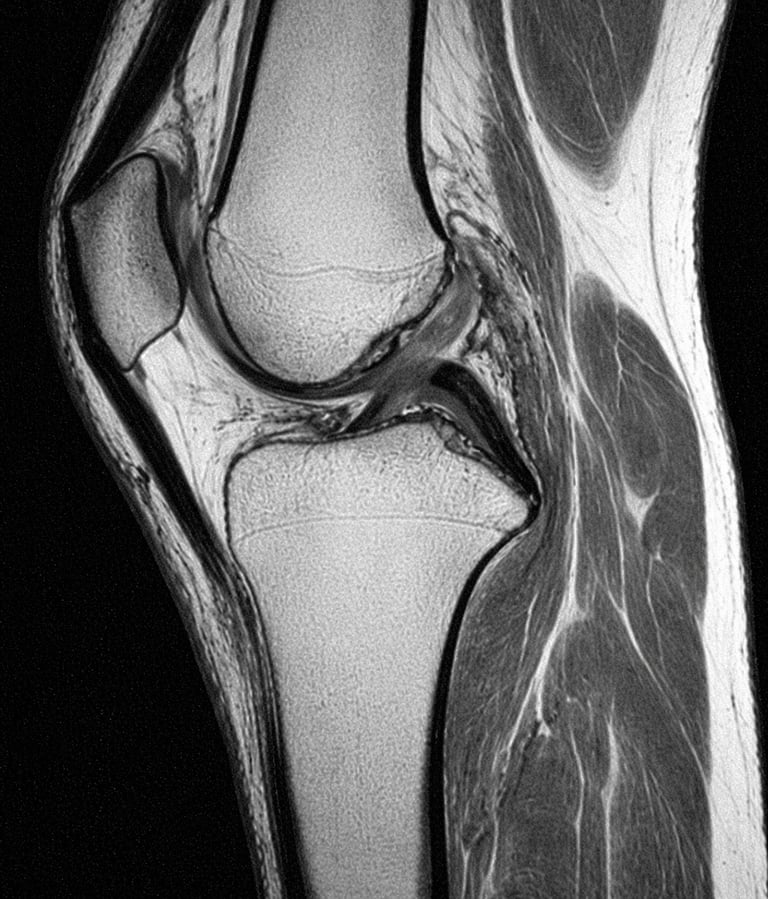

L’IRM du genou est un examen d’imagerie médicale qui permet d’analyser en détail les structures internes du genou.

L’IRM (Imagerie par Résonance Magnétique) est un examen qui utilise un champ magnétique pour obtenir des images précises du genou.

Elle permet de visualiser :

les ménisques

les ligaments

le cartilage

les tendons

l’os

Contrairement à la radiographie, elle permet d’explorer les tissus mous.

Que montre une IRM du genou

L’IRM permet de détecter :

lésions du ménisque

rupture des ligaments

arthrose du genou

inflammation articulaire

épanchement de synovie

C’est un examen très précis pour le diagnostic.